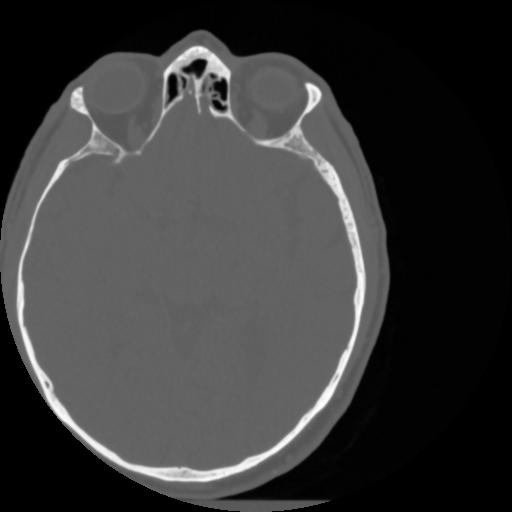

4 CEREBRO,,Vol,0.5,CEREBRO,,